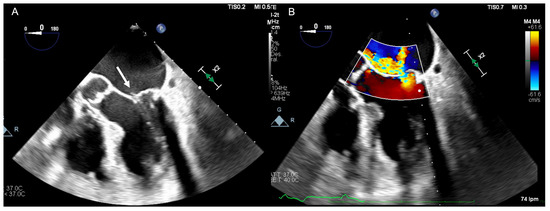

5. Diagnosis